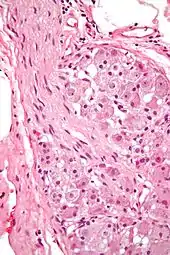

Ganglion cells within a ganglion. H&E stain.

In neurophysiology, a ganglion cell is a cell found in a ganglion (a cluster of neurons in the peripheral nervous system). Examples of ganglion cells include: